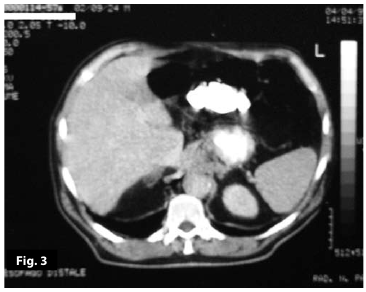

Figure3